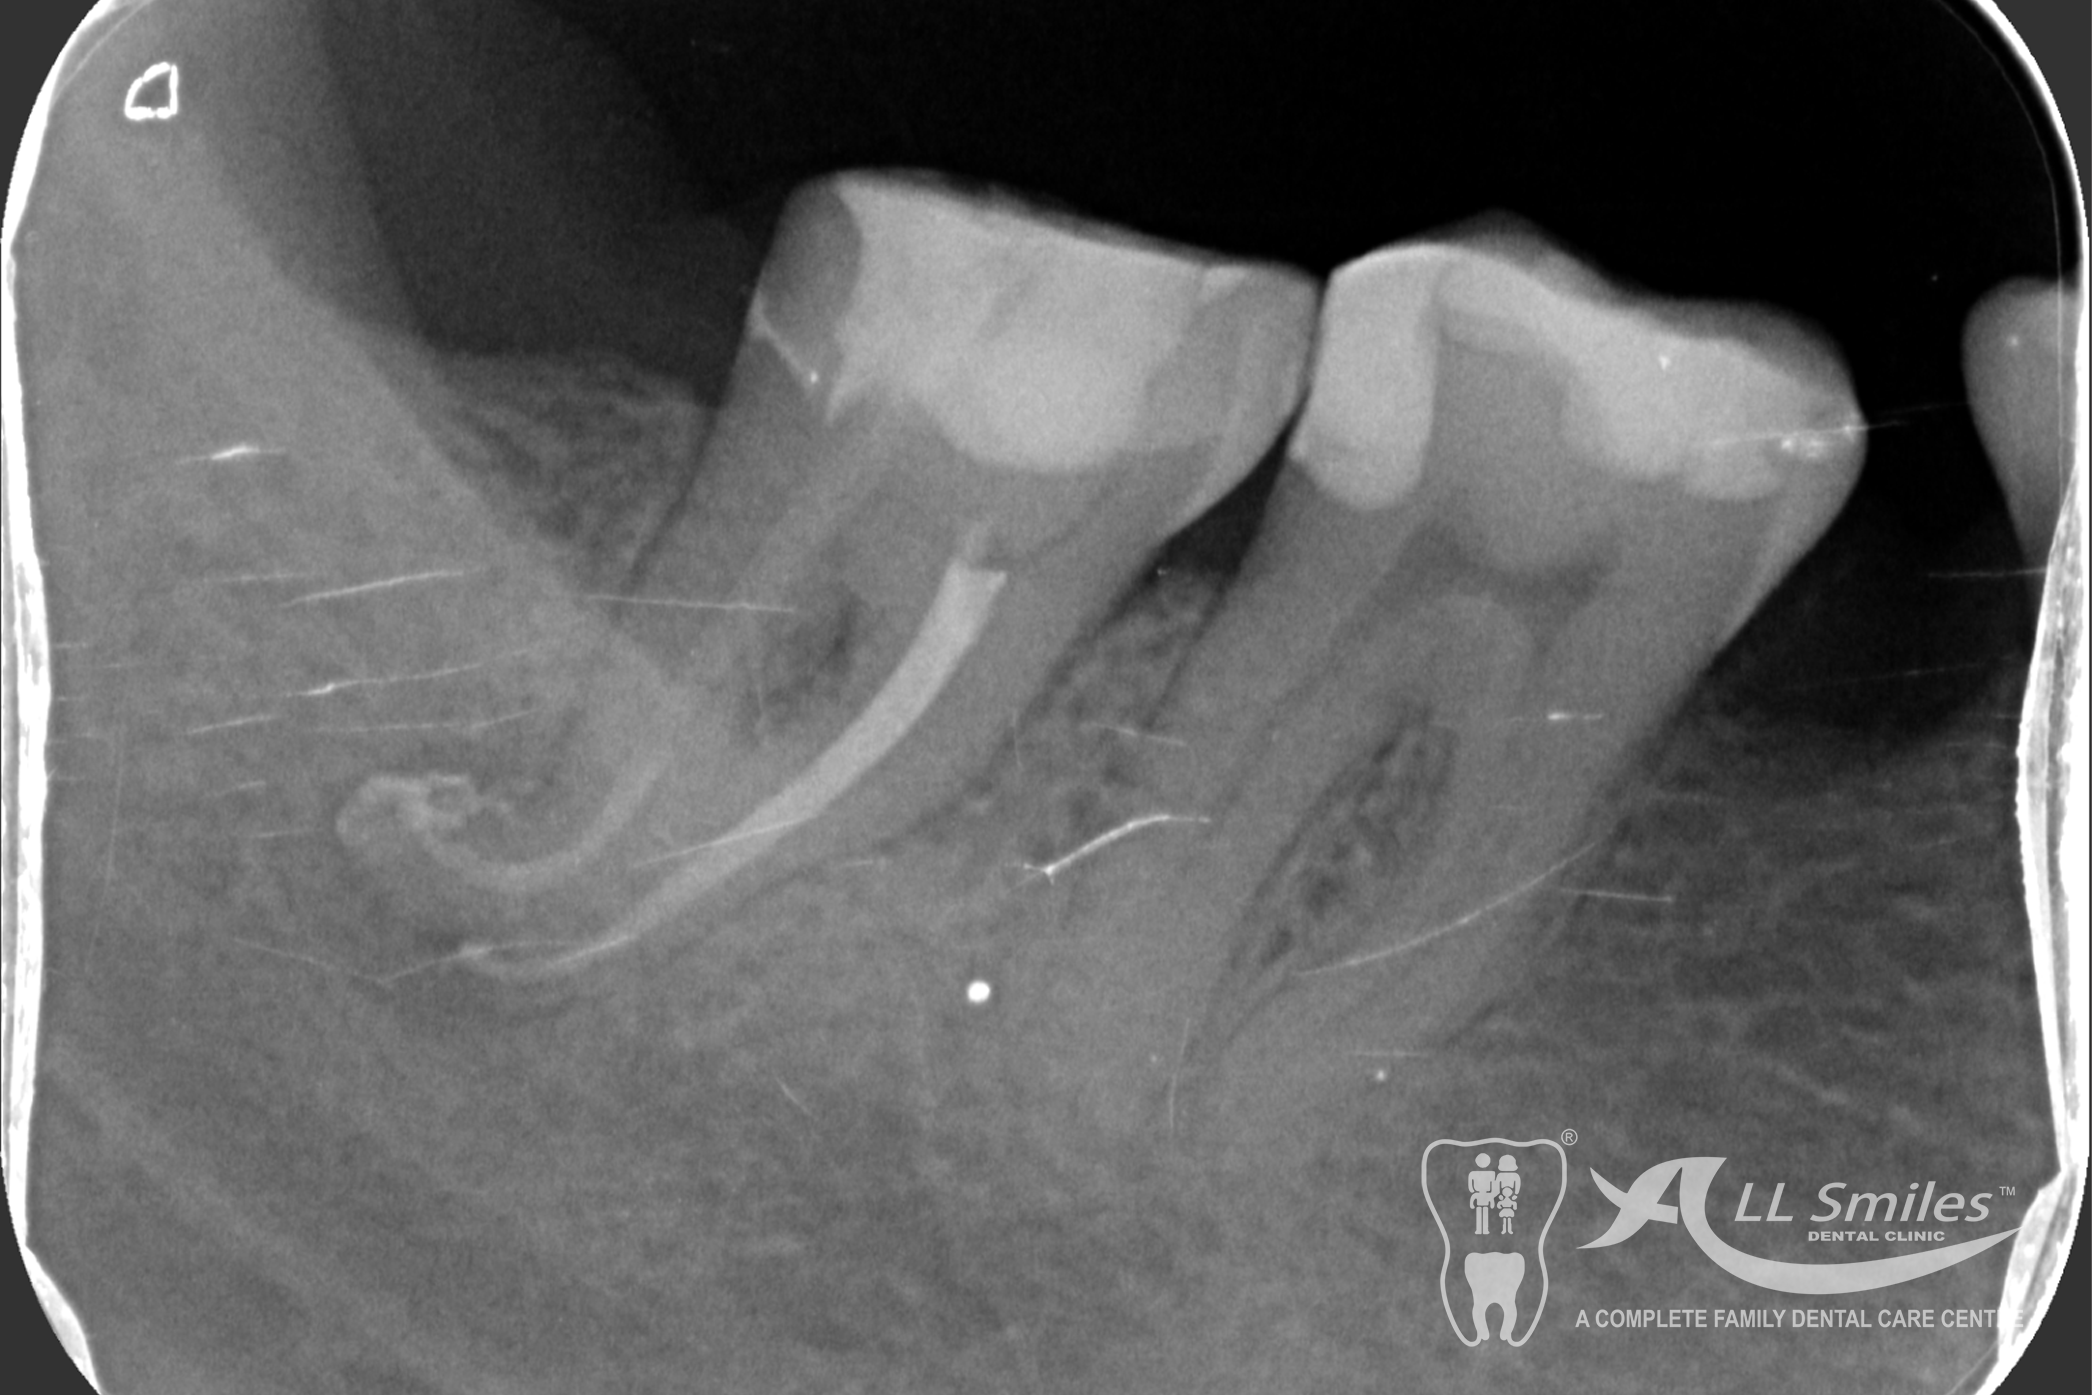

Root Canal Gallery